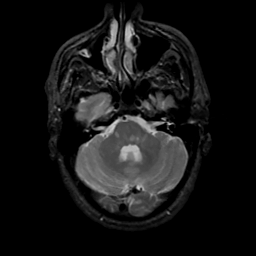

MR Study #16, June 23, 1991 -- Slice #12